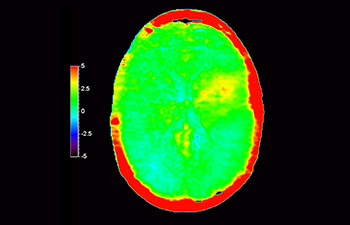

In a society where neurological disorders represent a heavy burden, Philips is committed to provide superb diagnostic clarity and treatment guidance for all patients. Today, although MR is the gold standard in neuro oncology imaging, its accuracy in tumor grading and treatment follow up assessment can be further improved. 3D APT (Amide Proton Transfer) is a unique, contrast-free, brain MR imaging method addressing the need for more confident diagnosis in neuro oncology. 3D APT uses the presence of endogenous cellular proteins, to produce an MR signal that directly correlates with cell proliferation, a marker of tumoral activity. 3D APT can support trained medical professionals in differentiating low grade from high grade gliomas and, in differentiating tumor progression from treatment effect1.

with 3D APT